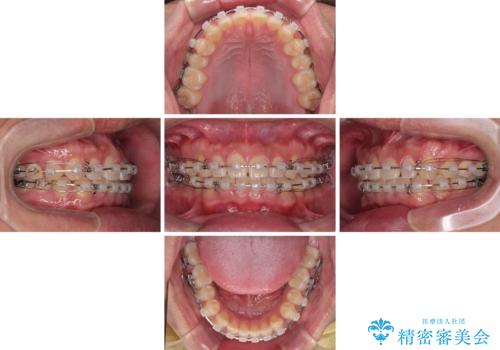

- 上下前歯の隙間を気にして来院された患者様です。

飲み込みや話をするときに舌を突出させる癖が強くあり、それが原因でスペースが空いていました。

舌癖を改善するためのトレーニングを行いながら、ワイヤー装置を用いて前歯の隙間を閉じていくこととしました。

舌のトレーニングをしっかりと行ってくださったおかげで、順調に治療を終えることができました。

舌の突出癖が速やかに改善され、後戻りによるスペースは今のところ認められておりません。